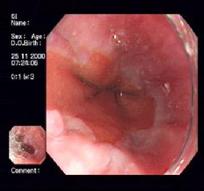

2.食管鏡檢查除休克或穿孔者外,應儘早施行,以判斷病變範圍,防止因狹窄而形成梗阻。需定期內鏡複查除進行擴張狹窄的食管外,及早發現食管癌,因癌的發生率比正常食管要高,尤其是強鹼致成的食管狹窄。腐蝕性食管炎一般根據其病史、症狀及體徵不難診斷,且常與腐蝕性胃炎並存。但在臨床中應注意是否合併有食管的其他病變。對於中老年男性患者而言,尤需注意與食管癌的鑑別。食管癌以吞咽困難、消瘦等為主要表現,病情呈進行性加重,X線及胃鏡結合活組織檢查可明確診斷。常將急性腐蝕性食管炎內鏡下表現分為3度:1度為黏膜充血水腫,可見小面積糜爛,但無出血,無滲出和潰瘍,黏膜脆性正常或僅輕度增加。此度損傷僅限於黏膜層,後期不會形成狹窄或其他嚴重併發症。2度為黏膜糜爛、滲出,脆性增加易出血,可有小面積潰瘍、壞死或黏膜剝脫。3度為大面積黏膜組織壞死、剝脫、出血,見大塊灰黑色焦痂樣物形成,或其他檢查發現縱膈炎、腹膜炎或肺炎等情況。食管腔可因水腫而明顯變小,或呈擴張狀態,無任何蠕動。有時較嚴重的2度損傷與3度損傷不易區分。